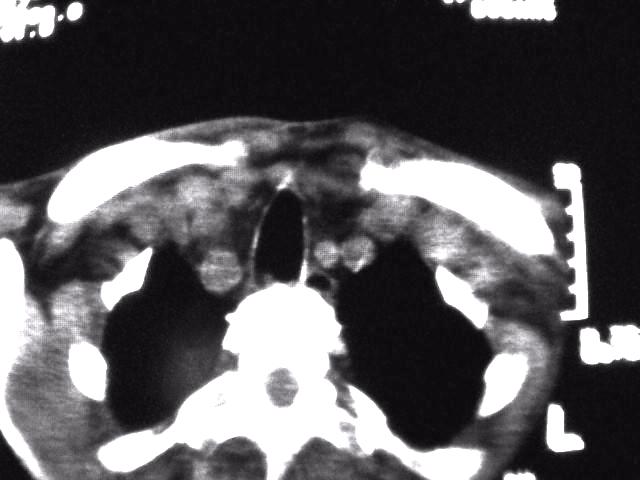

颈部层厚10mm间距10mm连续扫描及增强扫描共24层示:左侧下颈部胸锁乳突肌内侧区域内可见多发软组织结节,密度不均,内可见斑片状低密度区,大小不等,部分融合成块,左侧融合成一块者大约9.0x5.4,与周围肌肉、血管等结构界面不清,骨质未见明显浸润影。左侧锁骨下可见多个软组织结节,与周围界限尚清,左侧锁骨上窝内可见一大软组织肿物,大小约4.7x3.7cm,内密度欠均匀中心可见低密度区。

考虑:左侧颈部及双侧锁骨下多发淋巴结肿。非何杰金氏淋巴瘤可能性大,建议进一步检查。